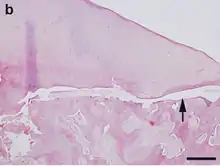

Hematoxylin and eosin staining. Bar = 200 μm.

OCD also is found in animals, and is of particular concern in horses, as there may be a hereditary component in some horse breeds.[97] Feeding for forced growth and selective breeding for increased size are also factors. OCD has also been studied in other animals—mainly dogs, especially the German Shepherd[98]—where it is a common primary cause of elbow dysplasia in medium-large breeds.[99]

In animals, OCD is considered a developmental and metabolic disorder related to cartilage growth and endochondral ossification. Osteochondritis itself signifies the disturbance of the usual growth process of cartilage, and OCD is the term used when this affects joint cartilage causing a fragment to become loose.[100]